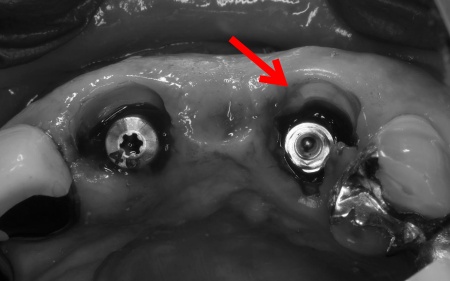

抜歯後に左上3本の欠損をブリッジで補う場合、多くの歯を土台として使用する必要があります。 ①インプラントを土台として、インプラントの上部にブリッジを装着する方法 ②欠損部位に取り外し可能な人工の歯を装着し、両隣の歯にバネをかけて固定する入れ歯 それぞれの治療方法について丁寧に説明したところ、患者様は「入れ歯を避けたい」との理由から、①のインプラントを選択されました。 【治療計画】 そこで今回は、抜歯と同時にインプラントを埋め込む抜歯即時埋入と、ご自身の歯質(歯を構成する成分)を唇側に残すソケットシールドテクニックを併用する治療を計画しました。 さらに、抜歯即時埋入と併用することで外科処置が1回ですむため、術後の腫れや痛みの軽減、治療期間の短縮、見た目や噛み合わせの早期回復も見込めます。 以上の治療計画について詳しく説明し、患者様に同意をいただいてから治療を開始しました。 【治療の流れ】 インプラントの埋入後は経過観察を行い、歯茎の治癒やインプラントと骨の結合を確認します。 後日、完成したブリッジをインプラントに装着し、噛み合わせをしっかりと調整して、治療を終了しました。 |

治療中